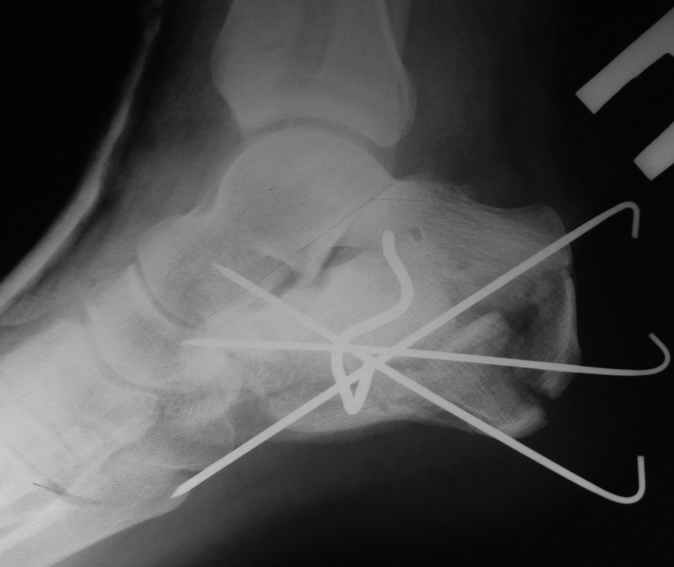

представляю снимки пациента с переломом пяточной кости. послеоперационный снимок этапный - по снятии швов спицы удаляю и наладываю циркулярную гипсовую повязку. к сожалению снимки с удаленной скобой представить не могу но поверьте на слово - консолидация полная, коррекция стойкая.

при планировании операции и ее исполнении выполнена костная аутопластика трансплантатом с гребня подвздошной кости причем трансплантат брался фрезой размером несколько болишим чем образованный в результате травмы дефект. скоба в данном случае обеспечивает компрессию между отломками-трансплантатом